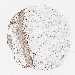

OVARIAN CANCER - Protein expressioni

A mouse-over function shows sample information and annotation data. Click on an image to view it in a full screen mode. Samples can be filtered based on level of antibody staining by selecting one or several of the following categories: high, medium, low and not detected. The assay and annotation is described here.

Note that samples used for immunohistochemistry by the Human Protein Atlas do not correspond to samples in the TCGA dataset.

Antibody stainingi

Antibody staining in the annotated cell types in the current human tissue is reported as not detected, low, medium, or high, based on conventional immunohistochemistry profiling in selected tissues. This score is based on the combination of the staining intensity and fraction of stained cells.

Each image is clickable and will lead to virtual microscopy that enables deeper exploration of all samples and also displays staining intensity scores, fraction scores and subcellular localization as well as patient and tissue information for each sample.

Antibody HPA031410

Staining

High

Medium

Low

Not detected

Intensity

Strong

Moderate

Weak

Negative

Quantity

>75%

75%-25%

<25%

None

Location

Nuclear

Cytoplasmic/membranous

Cytoplasmic/membranous,nuclear

Cystadenocarcinoma, serous, NOS

Carcinoma, endometroid

Cystadenocarcinoma, mucinous, NOS

Carcinoma, NOS